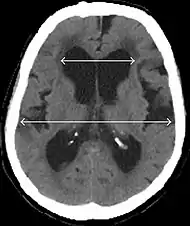

- Imaging from magnetic resonance imaging (MRI) or computed tomography (CT) is needed to demonstrate enlarged ventricles and no macroscopic obstruction to cerebrospinal fluid flow. Imaging should show an enlargement to at least one of the temporal horns of lateral ventricles, and impingement against the falx cerebri resulting in a callosal angle ≤ 90° on the coronal view, showing evidence of altered brain water content, or normal active flow (which is referred to as "flow void") at the cerebral aqueduct and fourth ventricle.

MRI scans are the preferred imaging. The distinction between normal and enlarged ventricular size by cerebral atrophy is difficult to ascertain. Up to 80% of cases are unrecognized and untreated due to difficulty of diagnosis.[10] Imaging should also reveal the absence of any cerebral mass lesions or any signs of obstructions. Although all patients with NPH have enlarged ventricles, not all elderly patients with enlarged ventricles have primary NPH. Cerebral atrophy can cause enlarged ventricles, as well, and is referred to as hydrocephalus ex vacuo.